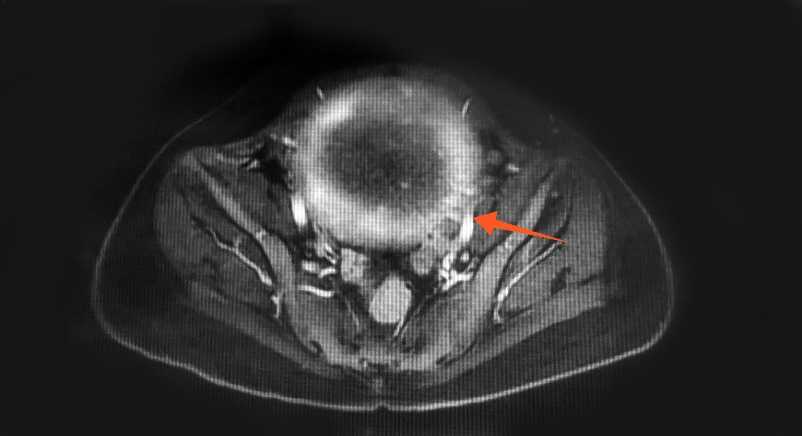

患者女,37岁,因“左下肢肿胀1天”于2021年07月10日入中山大学第一附属医院。中山大学第一附属医院下肢血管彩超提示双下肢静脉提示深静脉血栓形成,肺动脉CT可见双肺多发血栓形成(图1)。患者经抗凝溶栓治疗1个月后,于2021年08月04日出现大量阴道流血,并于2天后于家中昏迷,遂于2021年8月6日入暨南大学第一附属医院,诊断为子宫肌瘤。患者近期无外伤史、无输血史、无血液系统疾病史,无吸烟、吸毒史,近期无口服短效避孕药史,未婚未育,2年来有月经增多、经期延长、痛经史(月经周期28天,经期9~10天),体重正常,BMI 21.6 kg/m2。查体:生命体征平稳,贫血貌,宫底平脐上二横指,表面光滑,质硬,边界清,活动性差;双附件未触及。左下肢均匀凹陷性水肿,伴轻微疼痛,左下肢周径分别为左小腿39.5 cm (右侧37 cm),膝盖47 cm (右侧42.5 cm),大腿59 cm (右侧55.5 cm)。双下肢彩超提示:左侧大隐静脉根部及左侧股总、股浅、腘静脉血栓形成(图2)。B超提示:子宫体积增大,切面内径175 mm × 118 mm × 140 mm,实质回声欠均匀。内膜显示不清。宫腔内见一不均质低回声团,大小约117 mm × 146 mm × 117 mm,边界尚清。宫底肌层见一个实性低回声团,大小约44 mm × 56 mm × 48 mm,形状呈椭圆形,内部为低回声,分布均质,边缘清楚。盆腔MR提示:子宫后壁肌层见巨大类圆形异常信号影,大小约14.9 cm × 9.8 cm × 14.2 cm,病灶与子宫后壁肌层分界不清,增强扫描呈明显不均匀强化,考虑子宫平滑肌瘤与子宫平滑肌肉瘤相鉴别(图3)。血浆D-二聚体定量4270 ng/ml,血红蛋白HGB 61.30 g/L,蛋白S17.7%,抗磷脂抗体未见明显异常。入院后予缩宫素促进子宫收缩、促性腺激素释放激素激动剂(Gn-RHa)止血、生血宁纠正贫血、补液、输血、抗凝等对症处理后转介入科治疗血栓。于2021年8月16日行左下肢静脉造影 + 下腔静脉滤器植入术(图4)。DSA显示:左下肢股静脉、股总静脉上段、髂静脉、下腔静脉未见显影,股、髂静脉周围可见大量侧枝循环形成。术后予利伐沙班10 mg qd口服、升血宝15 ml tid + 红源达1片bid口服。患者病情稳定后复查CT示双肺肺动脉内多发血栓基本吸收,超声示肌瘤体积减小。遂于2021年8月30日在腰麻下行腹式子宫肌瘤剔除术,术中见子宫均匀增大如孕4月大小,质硬,表面光滑,宫底部见一带蒂浆膜下肌瘤,大小约60 mm × 50 mm × 50 mm。子宫及卵巢表面见炎性粘连带。术中病理冰冻结果:子宫平滑肌瘤伴玻璃样变性。手术顺利,两个肌瘤(总重量约900 g)在手术中被完全切除,未穿透子宫腔,术中出血约500 ml,患者未诉特殊不适。术后常规预防感染,低分子肝素抗凝治疗,复查患者血浆d-二聚体浓度降至670 ng/ml。术后4天取出下腔静脉滤器,患者活动后无不适出院,予利伐沙班口服半年预防血栓复发,并予Gn-RHa连续治疗3个周期,定期随访有无新发血栓形成。

Figure 1. Pulmonary artery CT: Multiple pulmonary thrombosis

1. 肺动脉CT:双肺多发血栓形成